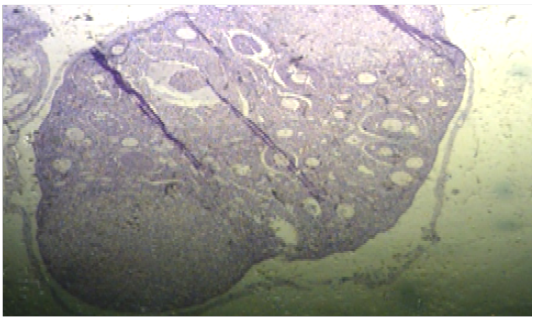

Histopathological section in ovary of G2 showed the cortex contained numerous follicles at various stages of maturation and corpus luteummore than G1 (H&EX40).

Histopathological section in ovary of G4 showed the cortex contained numerous follicles at various stages of maturation (H&EX400).

Histopathological section in ovary of G3 showed the cortex contained numerous follicles at various stages of maturation and corpus luteum, also contained lymphatics, nerves and numerous blood vessels (H&EX40)

Ovary section of G1 showed the cortex contained several follicles at different periods of maturation, medulla contained lymphatic’s, nerves and numerous blood vessels (H&EX40).